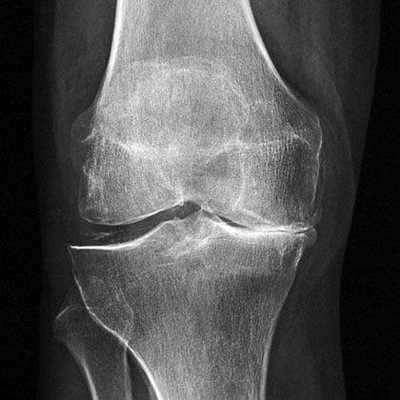

Динамика болезни на рентгене.

Откладывать хирургию при гонартрозах 3-4 степени чревато деформацией позвоночника. Это происходит из-за хромоты. Дегенеративные процессы артроза глубоко затронут кости, из-за чего они приобретут хрупкость, потеряют плотность и зафиксировать к ним компоненты импланта станет сложно.